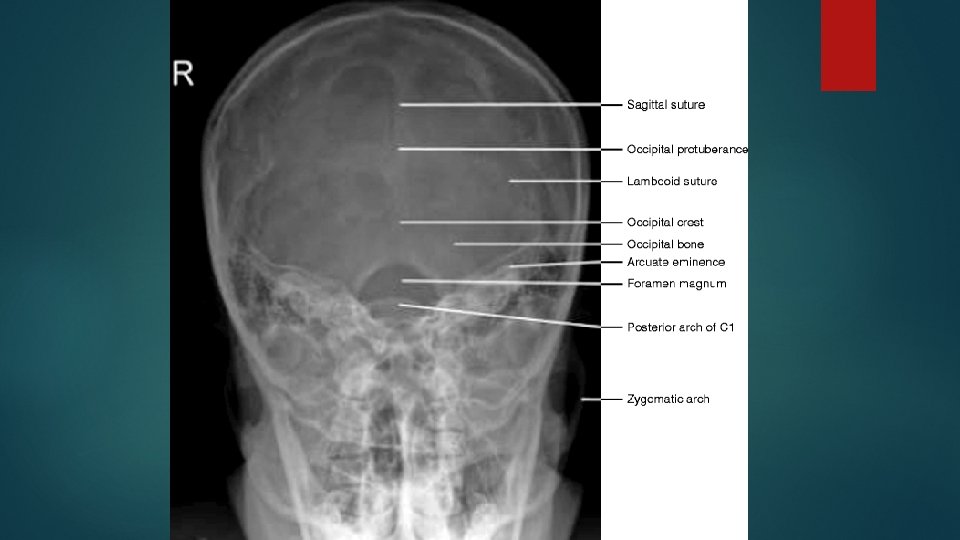

Towne’s view fronto occipital 30 deg caudad Positioning same as AP view Certral ray : Its angled caudally so it makes 30 deg to the orbito meatal plane Centre in the midline such that the beam passes midway between external auditory meatuses. This is a point approx 4 cm above the glabella

Essential image characteristics the sella turcica is projected with in the foramen magnum. Include all the occipital bone and posterior parts of parietal bone, and the lambdoid suture should be visualized clearly.